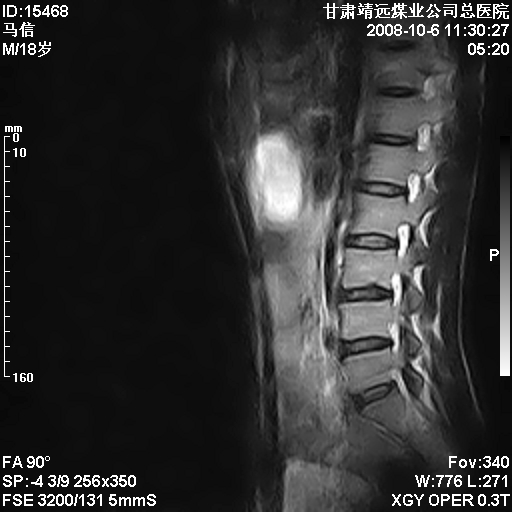

患者18岁,学生,在玩耍中受伤来检查,患者喜欢打篮球。颈椎内异常信号影,我们考虑占位,但是不像占位,又考虑硬膜囊的增厚,大家关建看颈椎椎管内的那个异常占位信号

腰椎的改变是不是正常发育的改变,还是打篮球的长期慢性损伤。

考虑 c3-4 c4-5 c5-6椎间盘突出,l3-4 l4-5 l5-s1椎间盘变性

颈椎建议做增强扫描;腰椎诸椎终板骨骺炎。

脑脊液流动伪影?

后纵韧带增厚,颈2/3、3/4、4/5、5/6椎间盘变性、突出;椎体有旋转,提示椎小关节有问题;腰椎间盘变性,许莫氏结节。

后纵韧带增厚,颈2/3、3/4、4/5、5/6椎间盘变性、突出;椎体有旋转,提示椎小关节有问题。腰椎诸椎体终板骨骺炎可能性大!支持!

是正常的脑脊液波动伪影

脑脊液流动伪影

你说的占位是伪影。在我们医院1.5t和3.0t的mr上是经常看见的。